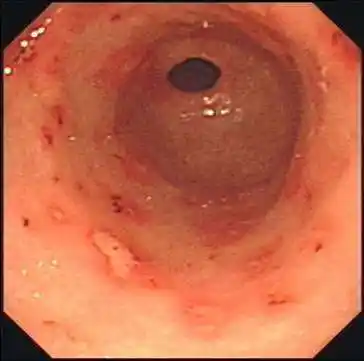

慢性非萎缩性胃炎伴出血,糜烂的图片 - 好大夫在线